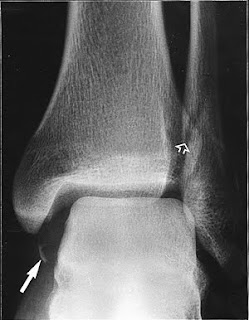

Avulsion fractures of the proximal fibula associated with knee ligament injuries or fibula fractures associated with ankle syndesmotic injury are much more common than isolated fibula fractures. Icd 9 code fx distal fibula avulsion.

The commonest classification is the weber classification that uses the position of the fracture relative to the syndesmosis to group fractures (803) other and unqualified skull fractures. (801) fracture of base of skull.

Injury and poisoning is one of the ranges international statistical classification of diseases and related health problems codes.

Coders will need very specific information in order to code for fractures. Isolated fibular fractures, when the ankle joint is unaffected, often can be treated with simple protection. (801) fracture of base of skull. 733.93 stress fracture of tibia or fibula. Following a severe fracture of my tibia and fibula, i share an update following 2.5 years of recovery. Fracture of vertebral column without mention of spinal cord lesion cervical, closed cervical, open dorsal open fracture of metacarpal bone(s) closed open fracture of one or more phalanges of hand closed open multiple. Classification of distal fibula fractures attempts to split fractures into groups by severity. Icd 10 distal fibula fracture, mishkanet.com. A bimalleolar fracture is a fracture of the ankle that involves the lateral malleolus and the medial malleolus. Below are 42 working coupons for distal fibula fracture icd code from reliable websites that we have updated for users to get maximum savings. Car accident back injury (bulging discs) and fibula fracture. Stress fractures of the fibula. Two bones make up the ankle.the ability to use a joint has nothing to do with it's fracture status. Icd 9 code fx distal fibula avulsion. Any modifying codes can designate fracture side, mechanism, and other characteristics. Cervical spine ct or cta reports were reviewed by two. 1090 x 1600 jpeg 80 кб.